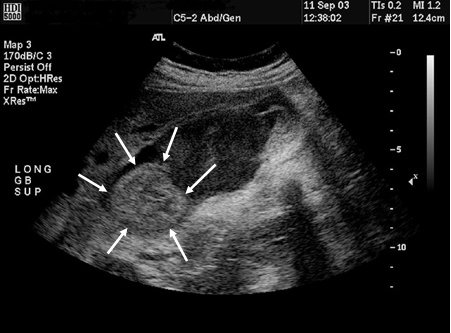

Cholangiocarcinoma

Gallbladder ultrasound of mass (arrows)

From the collection of Dr Joseph Espat; used with permission